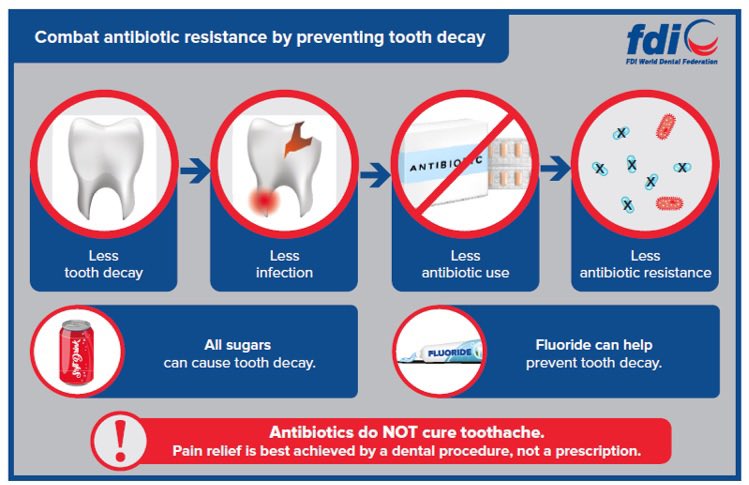

Prof. Dame Sally Davies Lesley Hawes MPH, PhD Tim Wainwright WaterAid UK 💦 Foreign, Commonwealth & Development Office Dental infections are some of the most common globally. Preventing dental infections through taxation on sugar sweetened beverages is recognised as an effective way of reducing antibiotic use and hence resistance.